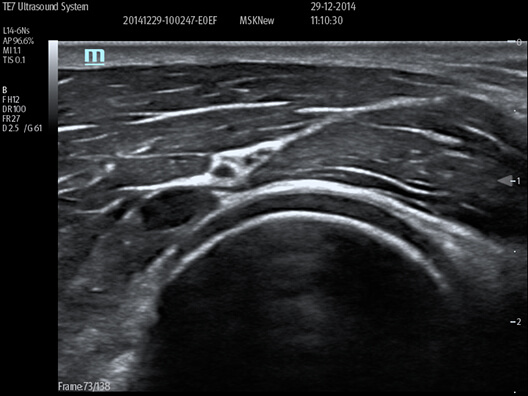

Urazy

Ułatwia znalezienie wolnego płynu w klatce piersiowej, osierdziu, jamie brzusznej i miednicy, aby pomóc wykonać badania FAST i eFAST.